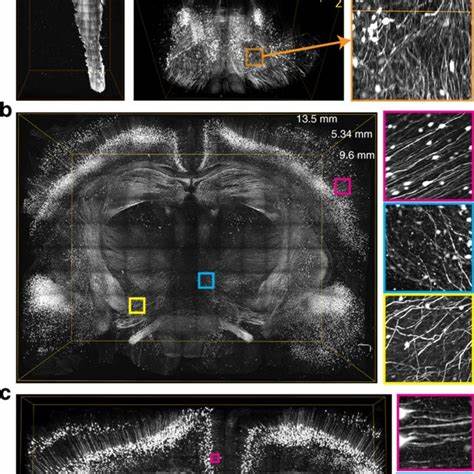

Изучение нервной системы всегда было одной из ключевых задач современной биологии и медицины. Сложность этой сети, состоящей из миллиардов нейронов и бесчисленных нервных волокон, требует чрезвычайно точных и современных методов исследования. Недавно ученые сделали важный прорыв, разработав высокоточный метод визуализации, который позволяет получать изображения нервных путей мыши с микрометровым разрешением. Этот инновационный подход открывает новые горизонты в изучении анатомии и физиологии нервной системы, позволяя детально проследить путь отдельных нервных волокон от мозга и спинного мозга до различных органов тела. Основную новизну данной технологии составляет высокая скорость сканирования при сохранении невероятной точности изображения.

Традиционные методы визуализации, такие как классическая микроскопия или МРТ, имеют ограничения по разрешению и времени обработки данных. Новый метод сочетает в себе современные оптические технологии с автоматизированными алгоритмами обработки, что позволяет получить карту нервных путей, детализированную до уровня отдельных волокон. Благодаря такой точности можно выявить не только крупные нервные пучки, но и мелкие ответвления, связывающие мозг со всеми частями тела. Концепция создания «картинки» нервной системы всего организма мыши является амбициозной задачей. Даже в силу относительно небольших размеров животного, сложность нейронных связей огромна и изучена далеко не полностью.

Благодаря высокоразрешающей микроскопии ученые получили возможность видеть, как ключевые нервы, например блуждающий нерв, взаимодействуют с разнообразными органами, регулируя их жизненно важные функции. В результате появляется перспектива создания полного провода нервной системы тела, своего рода «проводной схемы», которая бы помогала понять, как мозг управляет всеми физиологическими процессами. Помимо чисто фундаментальных научных задач, эта технология имеет значительный прикладной потенциал. Современная неврология и медицина постоянно сталкиваются с необходимостью понять причины заболеваний, связанных с нервной системой, таких как нейродегенеративные болезни, повреждения спинного мозга и расстройства периферической иннервации. Высокоточное картирование нервов с микроскопическим разрешением позволит выявлять аномалии в структуре и проводимости нервных волокон, своевременно диагностировать патологические процессы и разрабатывать целевые методы лечения.

Стоит отметить, что метод основан на комбинировании новых флуоресцентных меток, которые способны маркировать отдельные клеточные структуры, с продвинутым оптическим оборудованием. Это дает ученым возможность как визуализировать путь нервных волокон, так и одновременно оценить активность определенных микрокомпонентов, отвечающих за передачу сигналов. Такая функциональная визуализация может стать ключом к разгадке механизмов работы нервной системы и её адаптации к внешним и внутренним стимулам. Полученные данные уже публикуются в авторитетных научных изданиях, таких как журнал Cell, подтверждая серьезность и новаторство проведенных исследований. Глобальное научное сообщество активно принимает этот метод, расширяя его применение на другие модели животных и, в перспективе, на человеческую нервную систему.